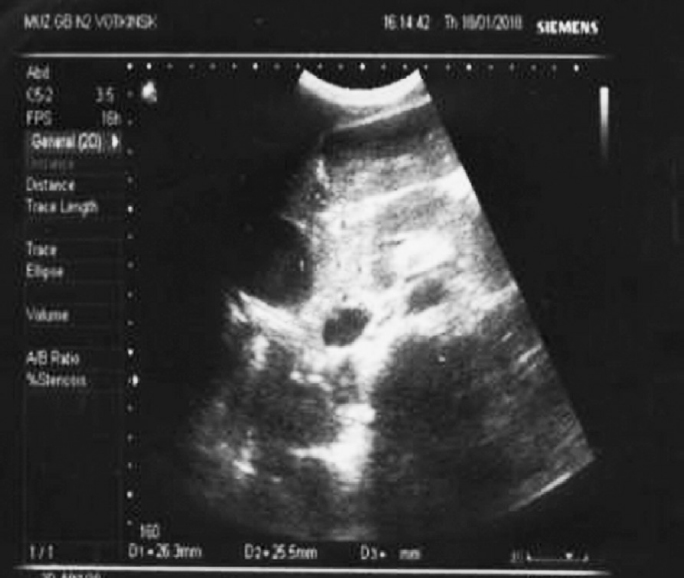

Затем вновь отмечалось появление болевого синдрома. Повторно проведено УЗИ, на котором было выявлено образование в области головки ПЖ (рис. 1) и расширение вирсунгова протока (рис. 2). От госпитализации в городскую больницу мать отказалась.

Рис. 1. Ультразвуковое исследование органов брюшной полости ребенка с аутоиммунным панкреатитом: опухолевидное образование поджелудочной железы

Fig. 1. Ultrasound examination of abdominal cavity organs of a child with AIP: tumor-like formation of pancreas